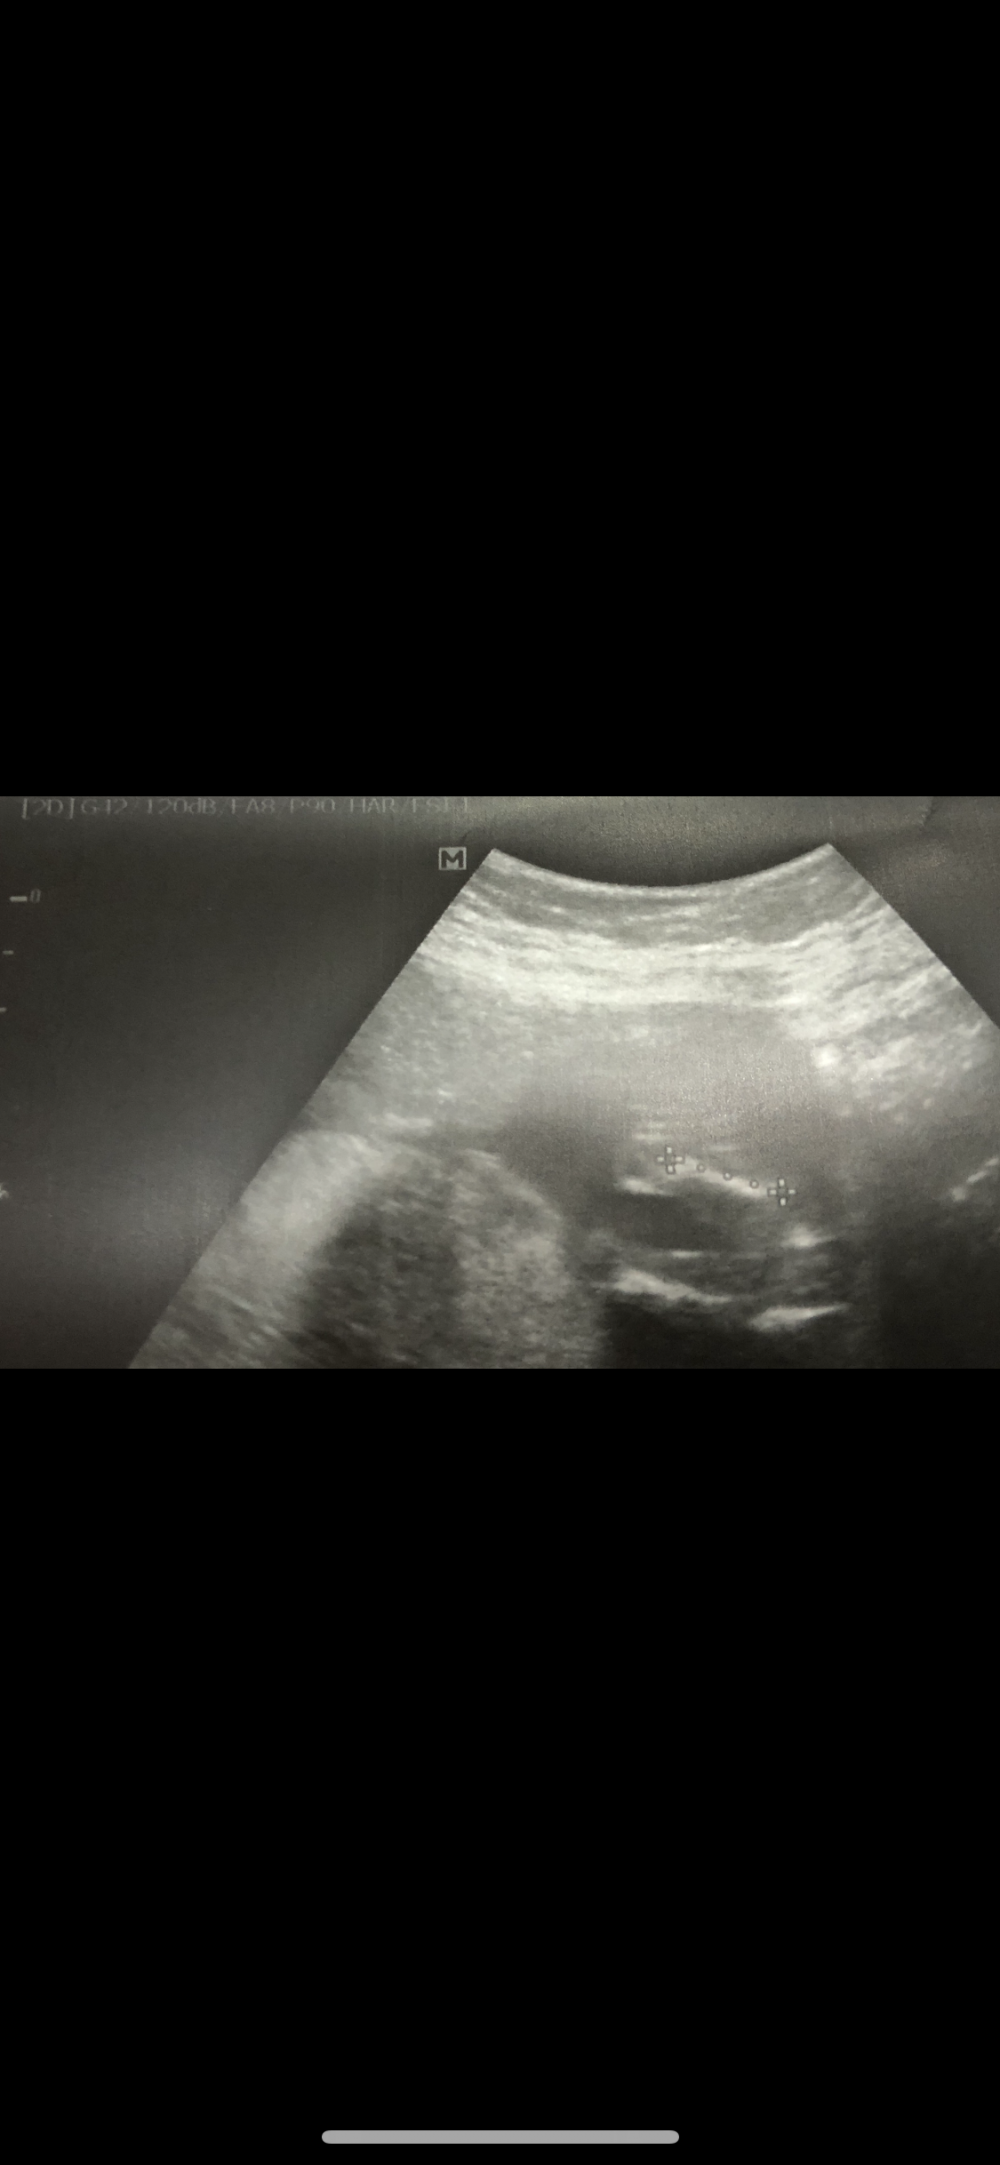

القمر اسمي قمر :

السلام عليكم حوائيات من زمان متابعتكم وهذي اولى مشاركاتي ياريت تضيفوني معكم موعد ولادتي بيكون ٢٥/٣/٢٠١٩ بإذن الله الحمد لله والشكر اليوم كانت عندي مراجعة والدكتورة تقول معاي ولد الله يسر حملنا وولادتنا اجمعينالسلام عليكم حوائيات من زمان متابعتكم وهذي اولى مشاركاتي ياريت تضيفوني معكم موعد ولادتي بيكون...